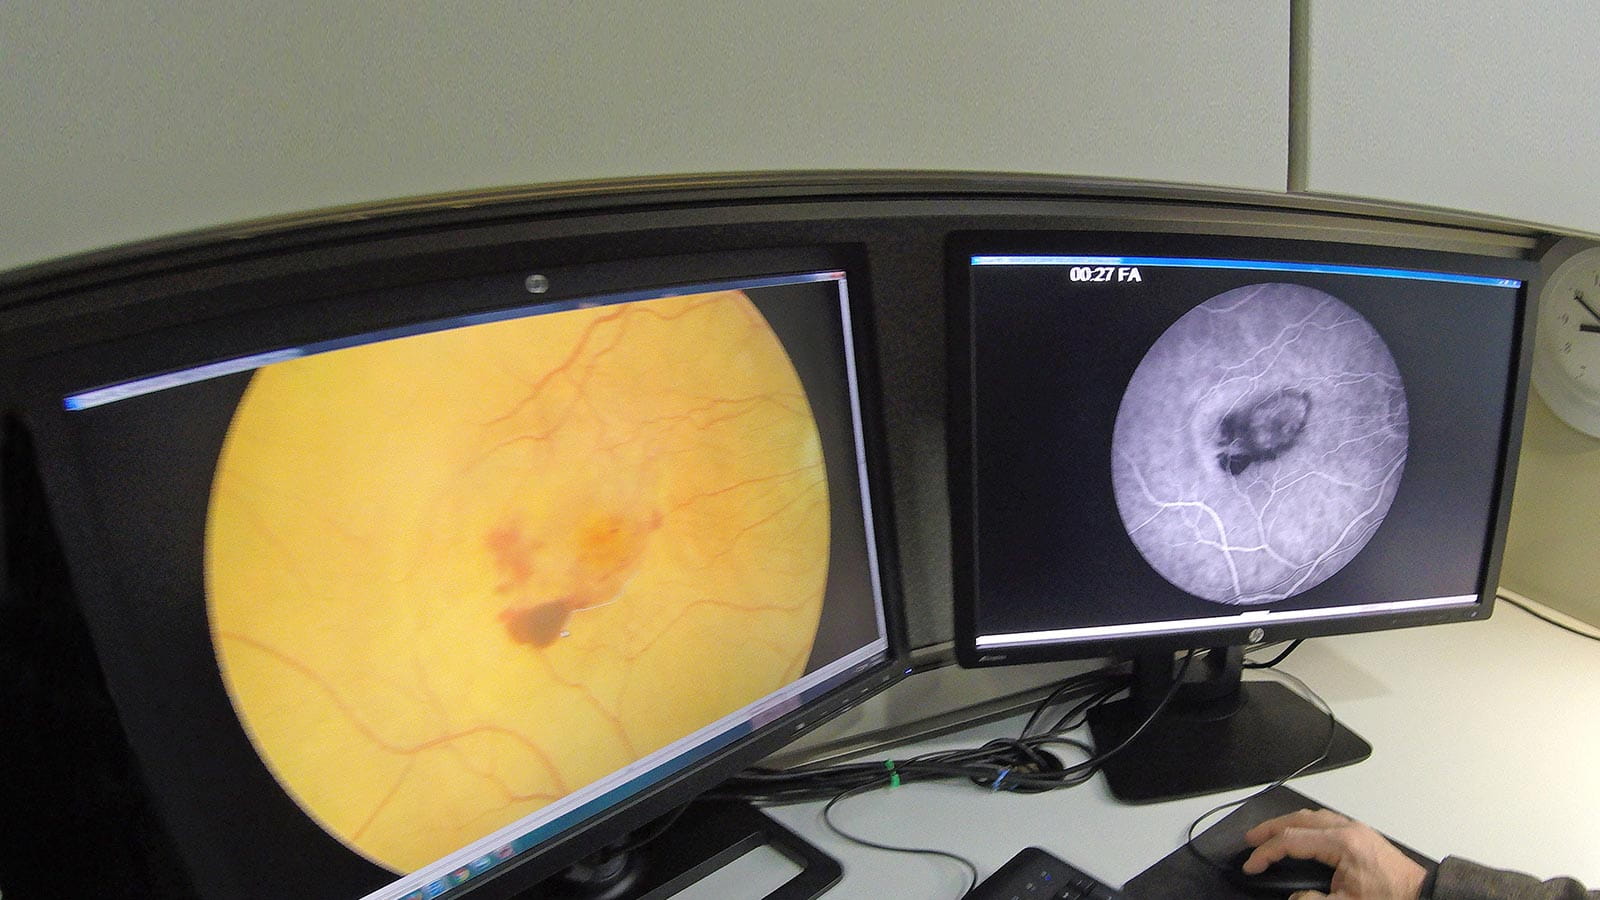

Retina Diseases Image Analysis Reading Center (REDIARC)

The Retina Diseases Image Analysis Reading Center specializes in evaluating retinal pathology using fundus photography, fluorescein angiography, autofluorescence and OCT. This center supports national and international clinical trials assessing therapies for diabetic retinopathy, macular degeneration and uveitis, ensuring precise and reproducible imaging outcomes.

Our expert readers assess parameters such as epithelial integrity including staining and defects, endothelial cell morphology, angle configuration, IOL positioning, lid abnormalities, and alterations in retinal structure in disease using modalities including external imaging, confocal microscopy, fundus photography, fluorescein angiography, meibography, optical coherence tomography, and specular microscopy. These standardized, protocol-driven assessments ensure consistency and accuracy across multicenter studies and imaging systems.  They are supported by novel AI-driven image analysis methods under development.